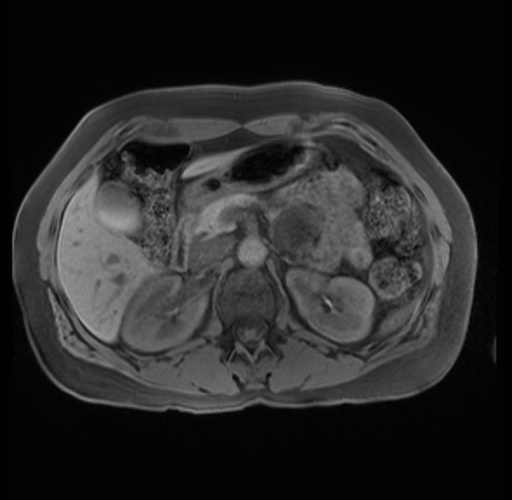

Imaging Analysis

Look through the patient's CT scan to identify any areas of concern for the necessary procedure.

Based on your CT findings, which issue(s) are present and would give reason for "planned slowing down moment(s)" in this case?